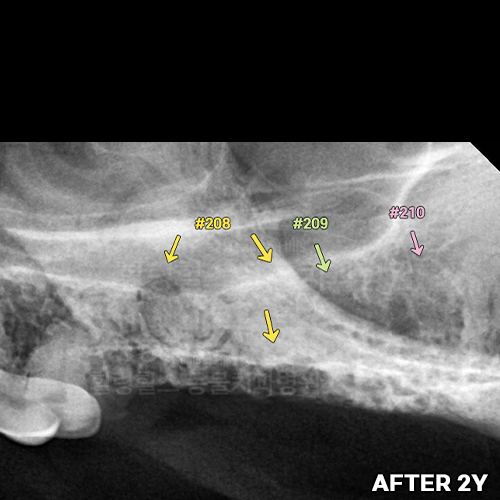

[최소침습적 발치 후 재생된 잇몸뼈 2년 후 모습]

샘플 샘플

[최소침습적 발치 후 재생된 강아지 잇몸뼈]

샘플